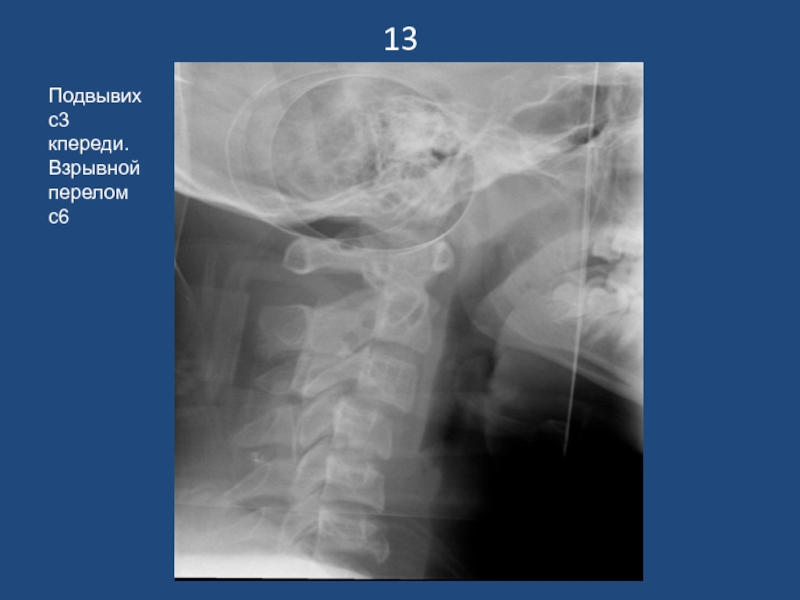

Слайд 1413

Подвывих с3 кпереди. Взрывной перелом с6

13Подвывих с3 кпереди. Взрывной перелом с6